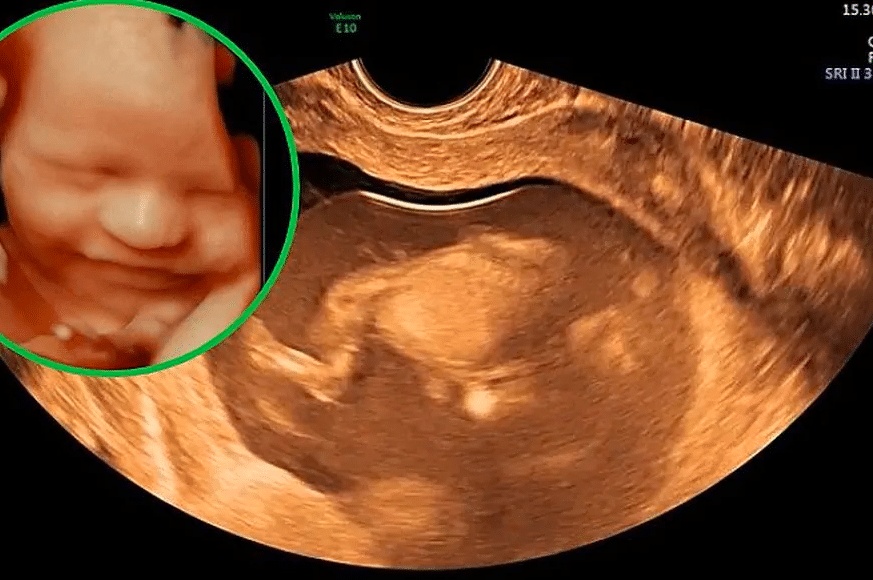

• يعتمد فحص مسح أعضاء الجنين بالسونار على استخدام الموجات فوق الصوتيّة، إذ تُبَثّ الموجات الصوتية باتجاه الرحم، ثمَّ تستوعب الموجات المرتدّة، بعدها تُتَرجم جميع الإشارات إلى صورة على جهاز الحاسوب، ويُمكن من خلالها مشاهدة أعضاء الجنين، وفي معظم الحالات يُجرى المسح المبكّر من خلال المهبل، بينما يُجرى المسح المتأخّر من خلال البطن.

• وفي كلتا الحالتين يستغرق الفحص فترة زمنية تتراوح ما بين 20-40 دقيقة، ومع ذلك يرتبط هذا الفحص ارتباطًا وثيقًا بوضعيّة الجنين في بطن أمّه، بالإضافة إلى خبرة الطبيب الذي يفحص، وعوامل أخرى تؤثّر على فترة إجراء الفحص، وتجدُر الإشارة إلى أنَّ الطبيب يُحدّد في هذا الفحص حجم الجنين، ويفحص سلامة الأعضاء، مثل القلب والأطراف والعمود الفقري والحبل السرّي.